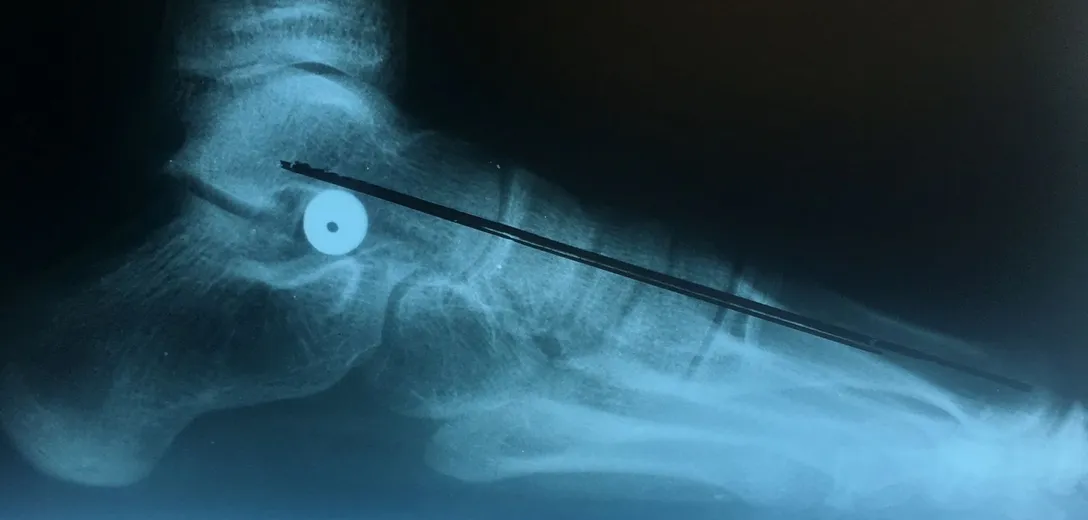

Pre-operative x-rays of the flatfoot with the talus deviated medially due to subluxing off the calcaneus causing the midtarsal joint to sublux laterally and uncovering of the talar head at the talo-navicular joint (left). The talus bone should line up with or be close to paralletl with a line drawn through the 1st metatarsal shaft (right). This is referred to as Meary's angle.

One case see an improvement in Meary's angle after surgical repair of the flatfoot with a subtalar joint implant which blocks the subluxation of the talus off of the calcaneus.

Below are x-rays of a foot pre-operatively (left) where the black line indicates and plantarflexed (downward directed) talus bone and post-surgical repair with a subtalar joint implant and lenthening of the calf muscle which allows the calcaneus (heel bone) to set underneath the talus and the implant keeps the talus from subluxing off the calcaneus and now the talus is more inline with the front of the foot (right).